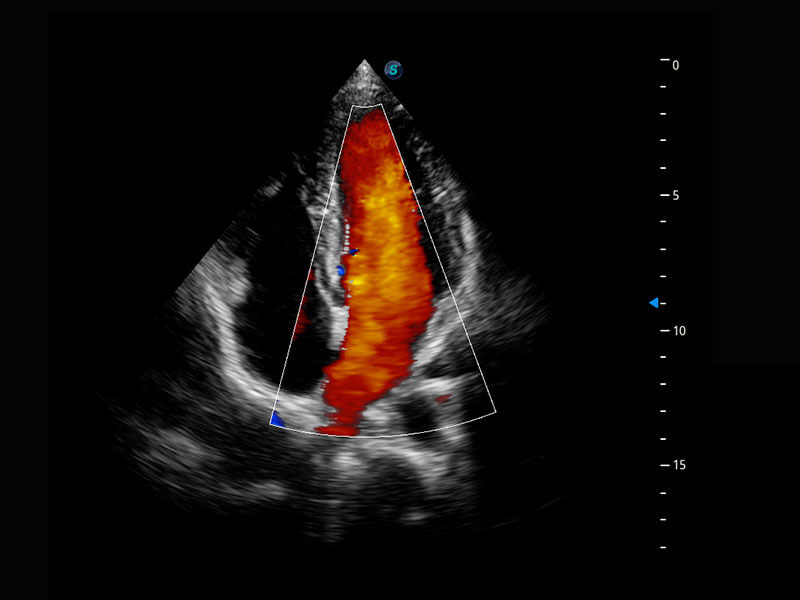

P60搭载一系列胎儿心脏成像技术,实现精细的胎儿心脏评估。

四腔心血流

右室双出口